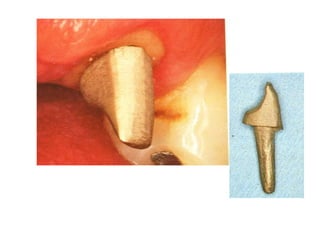

Post crown: it is an artificial

restoration of the coronal

portion of the natural tooth

maintained in position mainly

by post inserted in the

prepared root canal.

Post crown: itis an artificial restoration of the coronal portion of the natural tooth maintained in position mainly by post inserted in the prepared root canal.